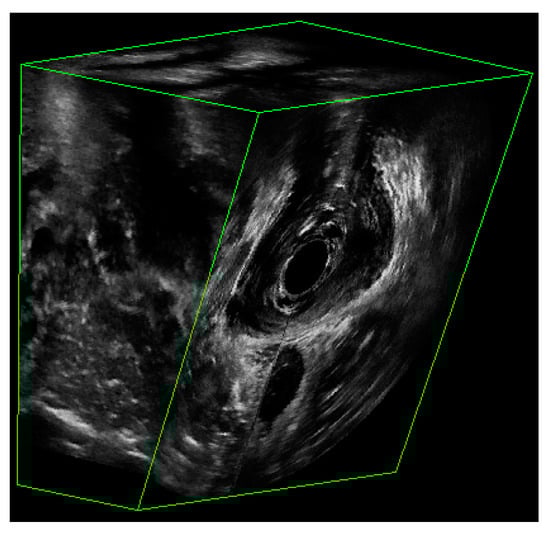

- Asif, Z.; Tomashev, R.; Peterkin, V.; Wei, Q.; Alshiek, J.; Yael, B.; Shobeiri, S.A. Levator ani muscle volume and architecture in normal vs. muscle damage patients using 3D endovaginal ultrasound: A pilot study. Int. Urogynecol. J. 2022. [Google Scholar] [CrossRef] [PubMed]